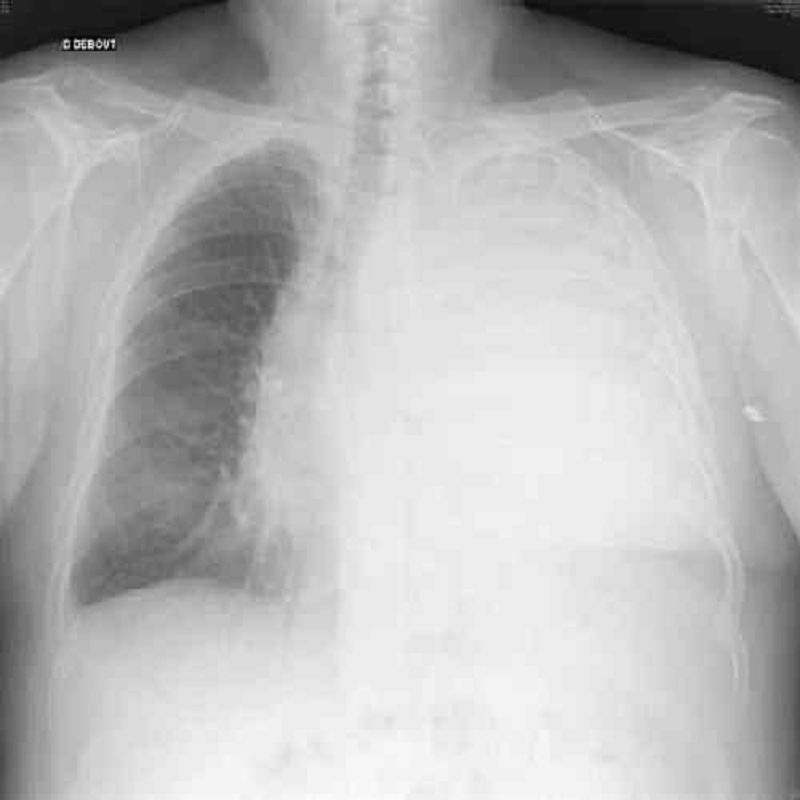

Vous voyez en consultation en urgence un patient de 65 ans pour dyspnée aigue. A l’examen clinique vous retrouvez une tension à 135/80 mmHg, une fréquence cardiaque à 95/min et une saturation à 91%. L’auscultation pulmonaire retrouve une diminution du murmure vésiculaire à gauche et une matité complète à gauche. Vous faites une radiographie pulmonaire en urgence dont voici le cliché. Quel est le diagnostic le plus probable ?

Pleurésie gauche compressive

Atéléctasie du poumon gauche

Pneumothorax gauche complet

Pneumothorax droit complet

Pneumomédiastin